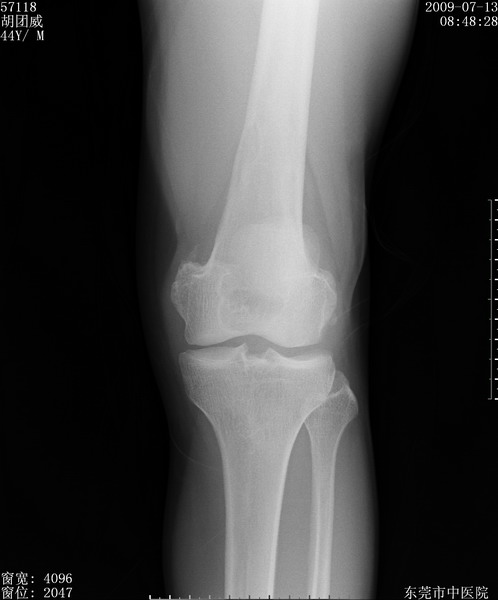

中年男性,膝韧带损伤术前检查!其他病史不清粗,不是我接手病人、且出院了!

1、股骨下段囊状膨胀性病变,边缘硬化明显,内多个残留骨棘呈多房型改变,囊腔密度较高无钙化,膝关节滑膜囊增厚,密度增高,关节腔少量积液。考虑:邻关节囊肿、退变性囊肿(软骨下囊肿)、着色性绒毛结节性滑膜炎、abc、骨巨、良性纤维组织细胞瘤等鉴。虽然年龄偏大,部位于骨端,但有外伤史,本人还是倾向于动脉瘤样骨囊肿(abc)可能性大。邻关节囊肿及软骨下囊肿次之考虑。

2、胫骨髁间棘撕脱骨折,交叉韧带损伤可能;

3、关节退行性改变。

病理结果:色素沉着绒毛结节性滑膜炎

感谢反馈病理结果!本病为慢性关节病变。以关节滑膜高度增生、绒毛结节形成伴含铁血黄素趁着为特点。病因:有炎症、肿瘤、外伤关节出血、代谢障碍、变态反应及感染等学说。增强扫描呈关节腔内单个或多个强化的软组织结节影或滑膜不规则增厚伴关节积液为本病的特征性表现。